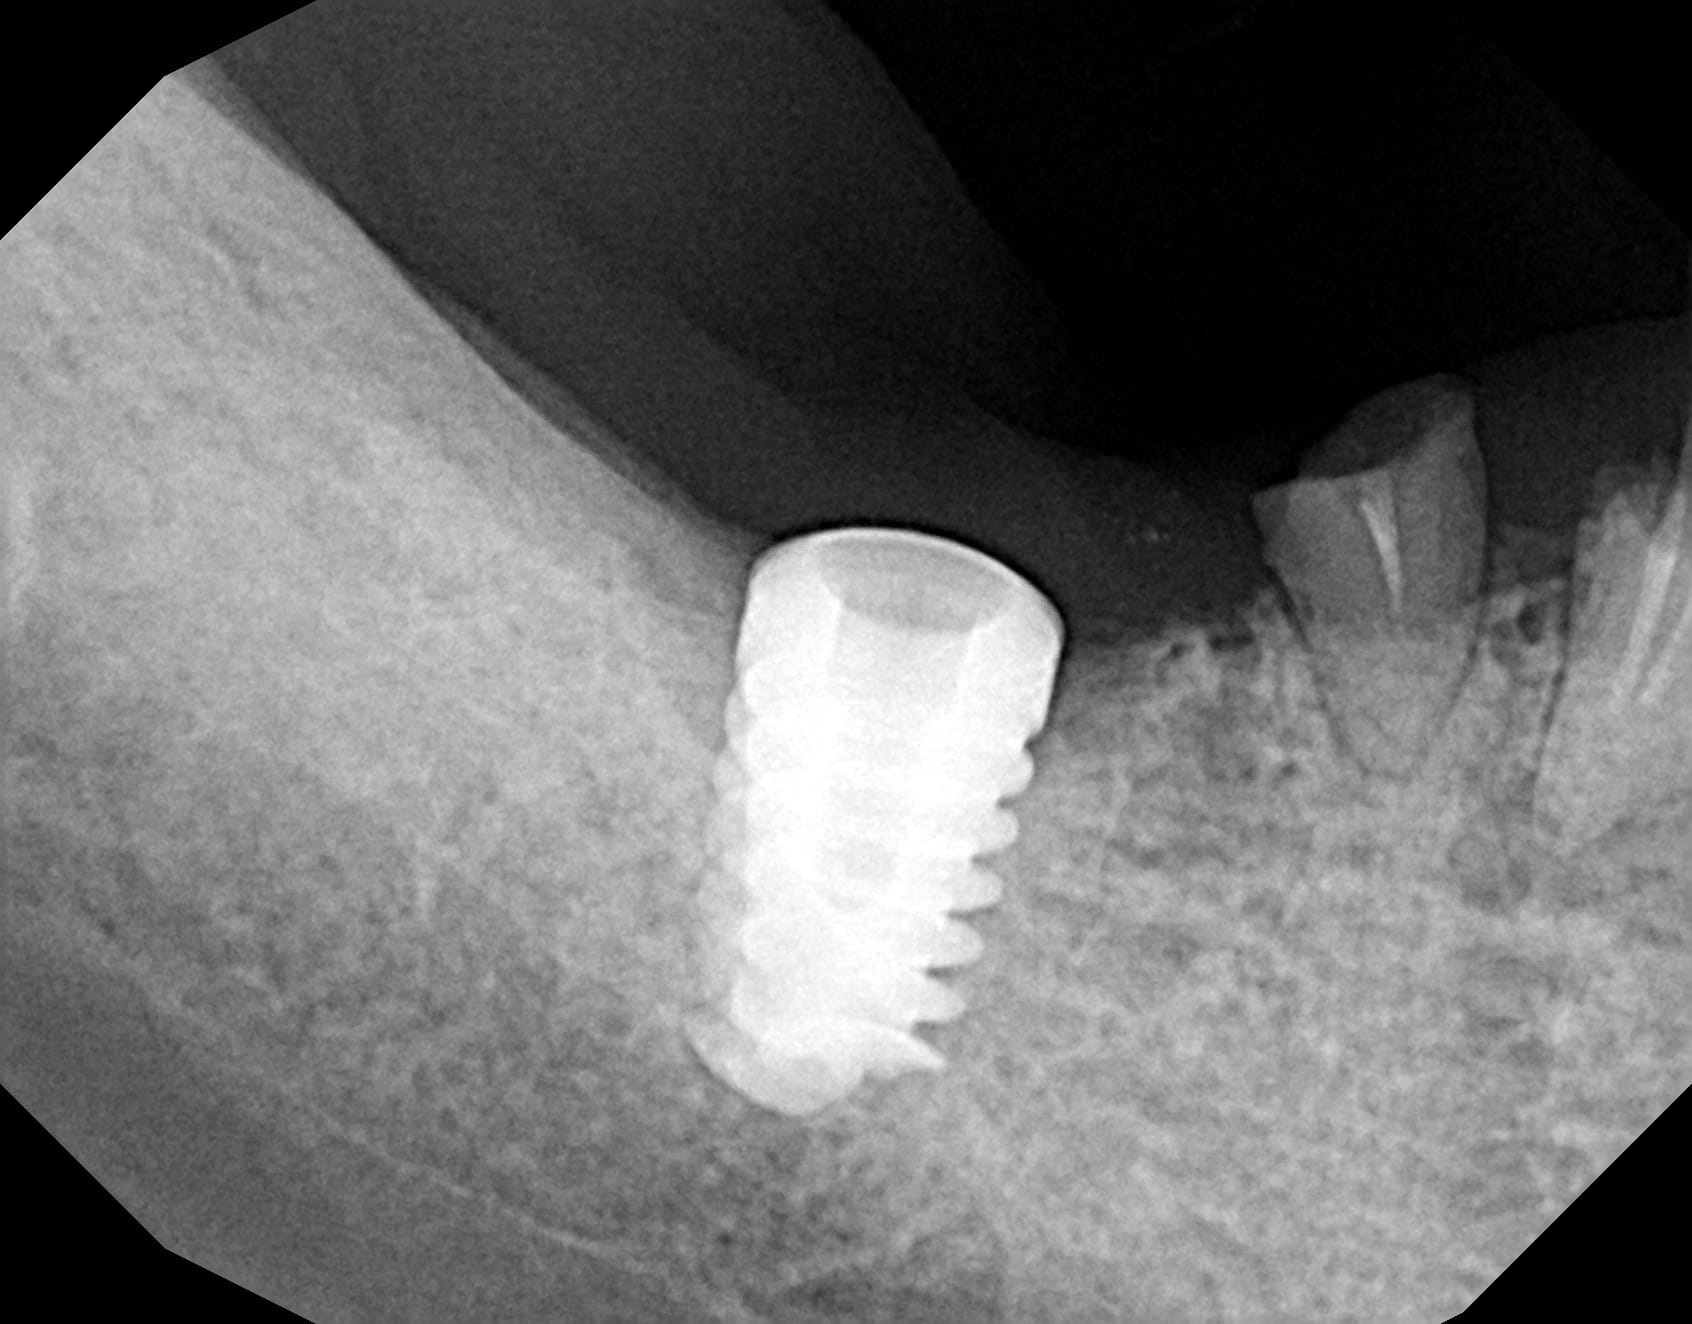

J'ai besoin de votre aide pour identifier cet implant posé il y a 4 ans dans une autre ville avant que le patient ne déménage et "oublie" de prendre soins de lui.

En fait la seule radio qui serait exploitable est la première…..mais comme elle est floue, je perds plein d’info….

Ce que j’ai trouvé de plus proche pour l’instant c’est l’implant conique de GC…..mais rien de certain….